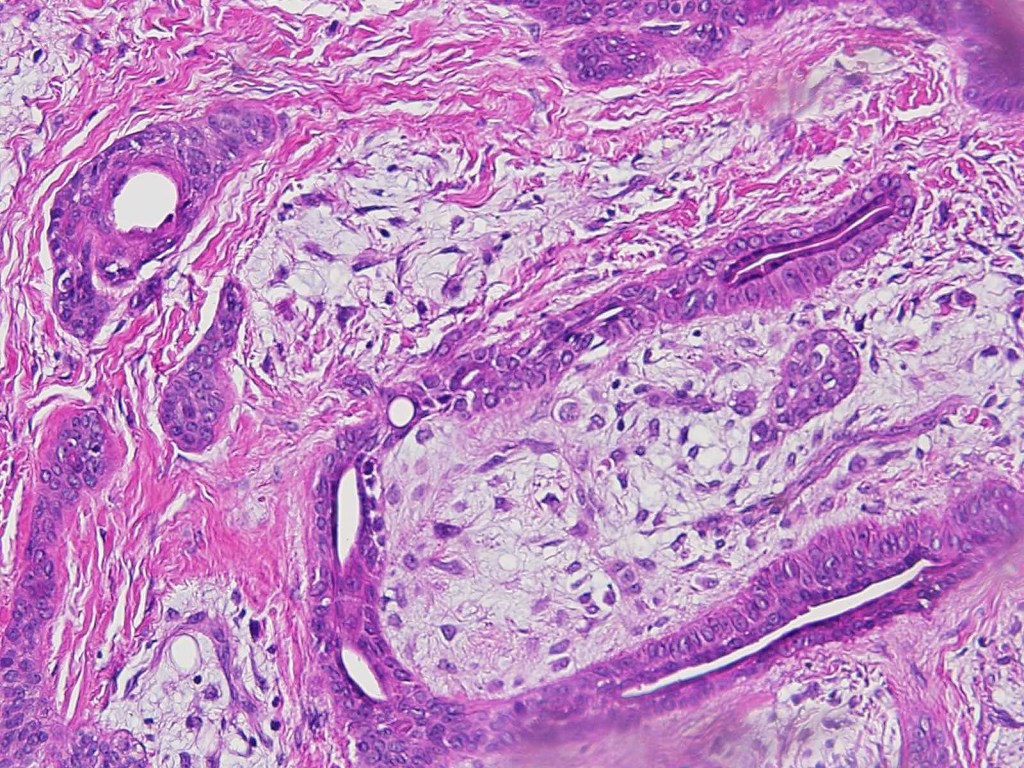

Histological features

•Well circumscribed unencapsulated, nodular/multinodular silhouette composed of an admixture of epithelial & mesenchymal elements

•Mixed epithelial component including nests & cords of epithelium with abundant, eosinophilic cytoplasm & small vesicular nuclei

•Clear cell change

•Glandular differentiation sometimes showing apocrine differentiation

•Myoepithelial layer in glandular foci

•Mucinous metaplasia

•Ductal differentiation

•Plasmacytoid myoepithelial cells; clear cell change

•Myxoid change

•Chondroid foci